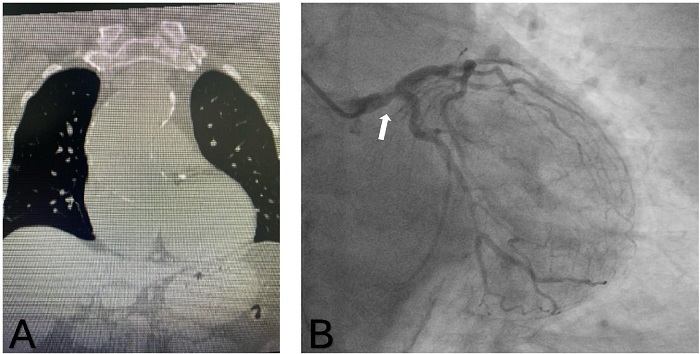

A 70-year-old female patient, with a medical history including stage IV kidney dysfunction, hypertension, type II diabetes, former smoking habits, and a previous stroke resulting in residual mild right hemiparesis, was transferred to our institution due to symptomatic severe aortic insufficiency in a New York Heart Association III/IV status, evidenced by transthoracic echocardiography with a regurgitant jet occupying 60% of the left ventricular outflow tract and a left ventricular ejection fraction of 55%. Preoperative computed tomography (CT) scan revealed a porcelain aorta with concurrent aneurysms of the ascending portion (60 mm) and proximal arch (48 mm), while the aortic root appeared normal (Figure 1A). Coronary angiography indicated 80% stenosis in the main trunk and 70% stenosis in the proximal left anterior descending artery (Figure 1B). The patient's case was discussed by a Heart Team, and a percutaneous strategy was declined due to the presence of an ascending aortic aneurysm and left main coronary artery stenosis. The study was approved by the hospital ethics committee (SSMOriente190324) and informed consent was obtained.